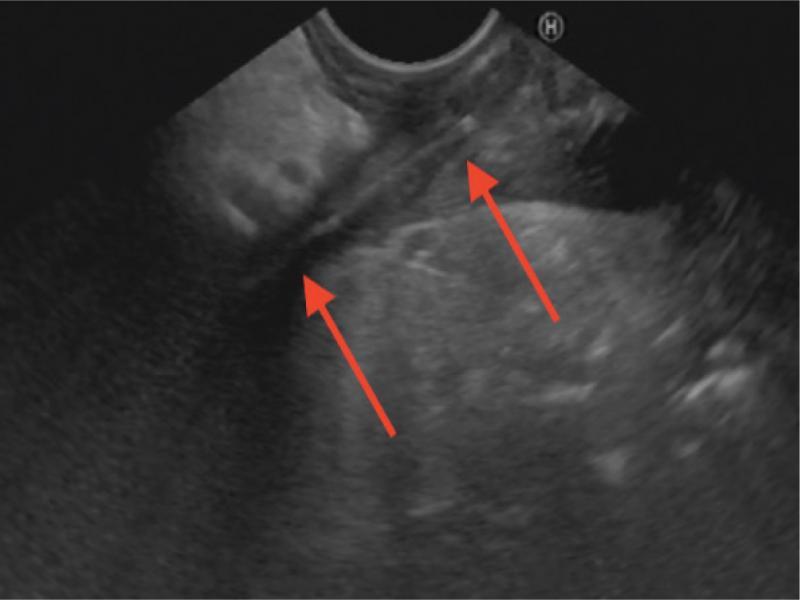

In the next step, gastroscopy was performed endoscopically, showing no obvious abnormalities. An EUS ultrasound image confirmed the presence of a linear foreign body stuck (5.6 mm deep from the ultrasound probe surface) in the muscular layer of the antrum. A precise evaluation of the extent of the lesion and surrounding structures was described (Fig. 2).

Fig. 2.

Endoscopic ultrasound, Hitachi Avius, Pentax EG-3870 UTK, transgastric approach, arrows: toothpick